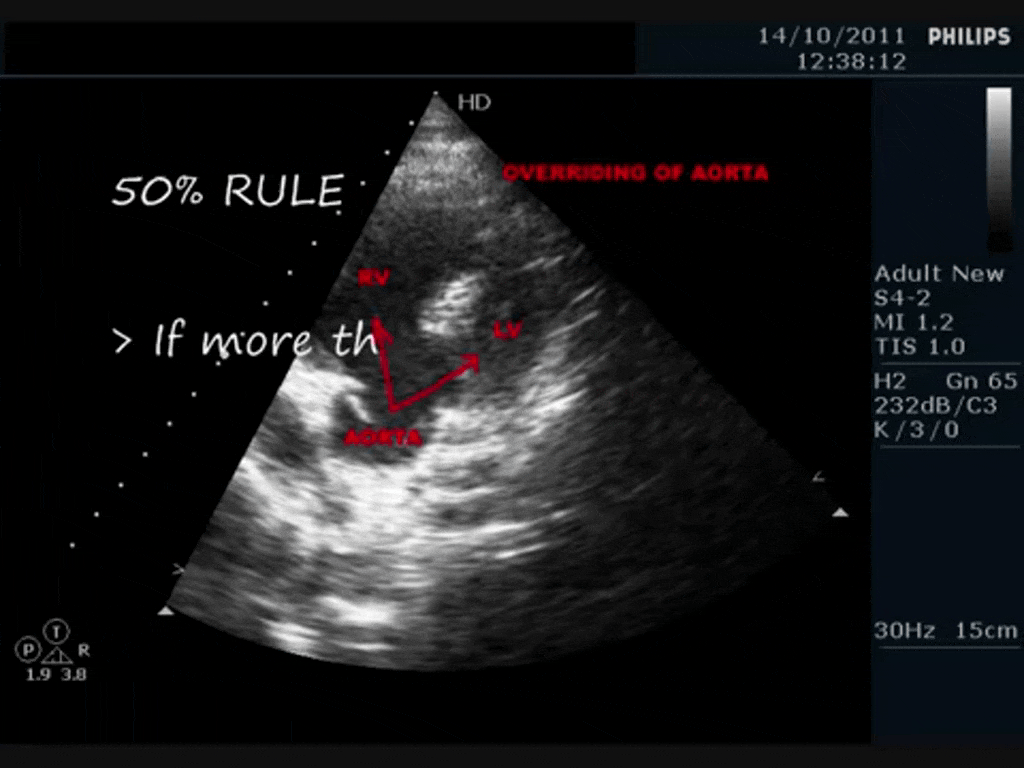

Tetralogy of Fallot Echocardiography

Echocardiogram overriding